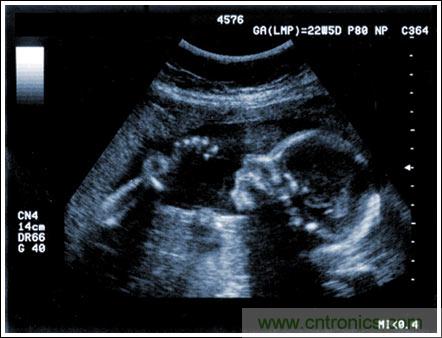

通過發(fā)射超聲能量進入人體,接收并處理返回的反射信號,相控陣超聲系統(tǒng)可以生成體內(nèi)器官和結(jié)構(gòu)的圖像,映射血液流動和組織運動,同時提供高準確度的血流速度信息。傳統(tǒng)設(shè)計中,構(gòu)建這樣的成像系統(tǒng)需要大量的高性能相控陣發(fā)射器和接收器,使得車載設(shè)備體積龐大且價格昂貴。近年來,隨著集成工藝的進步,設(shè)計人員能夠獲得小尺寸、低成本而且高度便攜的成像系統(tǒng)方案,并可達到接近大型成像設(shè)備的性能指標。而新的設(shè)計挑戰(zhàn)依然存在,即在進一步提高方案集成度的同時提高系統(tǒng)性能和診斷能力。